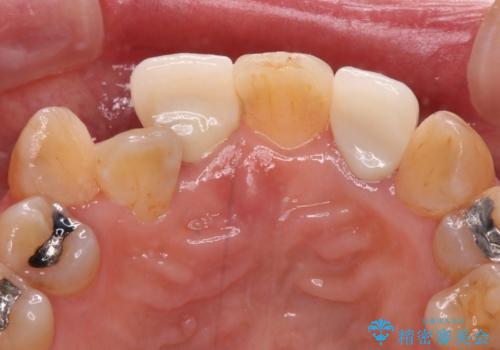

- 20年以上前に神経を取り除いた前歯の変色が気になるとのことで来院された患者様です。

レントゲン写真より、歯根の炎症が認められなかったため、ファイバーコアによる土台築製後、オールセラミッククラウンにて補綴することとしました。

また、真ん中の前歯はコンポジットレジンによる修復跡が目立っており、合わせてオールセラミッククラウンにて治療することとしました。